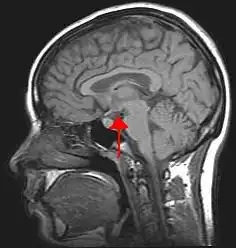

![]() Location of the human hypothalamus | |

![]() Location of the hypothalamus (cyan) in relation to the pituitary and to the rest of the brain | |

The hypothalamus (pl.: hypothalami; from Ancient Greek ὑπό (hupó) 'under' and θάλαμος (thálamos) 'chamber') is a small part of the vertebrate brain that contains a number of nuclei with a variety of functions. One of the most important functions is to link the nervous system to the endocrine system via the pituitary gland. The hypothalamus is located below the thalamus and is part of the limbic system.[1] It forms the basal part of the diencephalon. All vertebrate brains contain a hypothalamus.[2] In humans, it is about the size of an almond.[3]

Location of the hypothalamus